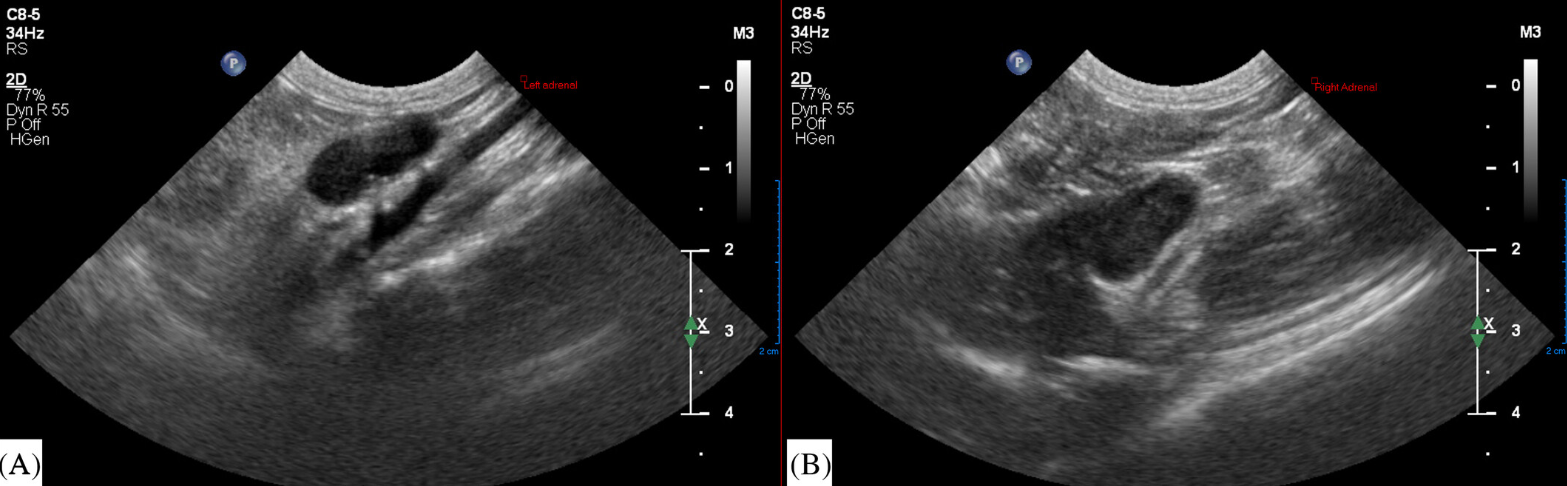

특히 주목할 소견은 초음파 소견인데 addison's disease를 언급하면 부신의 크기 감소가 반사적으로 나타나지만 이번 증례는 급성 부신괴사인만큼 염증으로 인한 부종으로 부신의 크기가 정상보다 더 커지는 것을 볼 수 있다. 또한 부종으로 인하여 에코의 감소 양상과 주변부 에코 상승을 동반하고 있는 특징을 볼 수 있다.

초음파로 최종 진단한것은 아니고 초음파 유도하 FNA를 통한 세포학 검사에서 뚜렷한 호중구 침윤을 관찰하여 adrenitis로 진단한 증례이다. 보통 한국의 수의사들은 부신에 대한 FNA에 대해 위험성이 너무 강조되어 두려워 하지만 필요할 때는 해야 하는 것이 어떤 의미에서 당연한 접근이다. 주변에 대동맥과 대정맥이 주행하고 있어 두렵지만 오히려 후복강에 위치하여 호흡운동에 영향을 받지 않는 장기이기 때문에 다른 장기들에 비해 옆구리 접근할 때 쉽게 FNA를 할 수 있는 장기이니 좀 더 자신감을 가지고 FNA를 일상화할 필요가 있다.